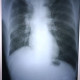

Alo dokter izin diskusi rontgen pasien paru berikut. Tn. M usia 54 tahun dengan demam 7 hari sudah pernah dirawat di klinik dan injeksi antibiotik demam masih naik turun. Sesak, suara nafas vesikuler menurun di lapang paru kanan. Riwayat merokok.

2. Gambaran radiologi menurut pengamatan saya: corakan bronkovaskular meningkat terdapat fibrosis pada kedua lapang paru, terdapat efusi minimal di lapang paru kanan( sudut costofrenikus menumpul minimal), jantung CTR <50%.

: - bagian Apeks Paru kanan atas tampak perselubungan Inhomogen yang meluas hingga para trakea kanan dan perihiler kanan diserta gambaran perselubungan homogen di Apeks paru kanan atas dan Efusi pleura kanan minimal

- Gambaran emphysematous lungPertanyaan :

Melihat foto thoraks di atas, menurut pendapat saya:

Dari posisi foto pasien dalam posisi asimetris saat di foto. Dapat dilihat dari sela iga kanan dan kiri nya berbeda (tampak lebih sempit di kanan) dan batas antara clavicula sisi medial ke junctional sternum kanan dan kiri tampak lebih lebar kiri.

Trakea: tidak tampak terdeviasi

Hilus: pada hilus kanan tampak melebar

Jantung: bentuk normal, ukuran dalam batas normal

Paru: tampak perselubungan opak di apeks paru kanan, batas tidak tegas. Tampak fibroinfiltrat pada batas jantung kanan.

Diafragma: diafragma kanan tampak meninggi dibandingkan kiri.

Pleura: pada sudut costophrenic kanan tampak tumpul.

Tulang-tulang: tidak tampak deviasi.

Kesan:

1. Suspek TB paru aktif disertai dengan infeksi pneumonia

2. Efusi pleura minimal kanan

3. Pelebaran hilus kanan kesan: pembesaran KGB